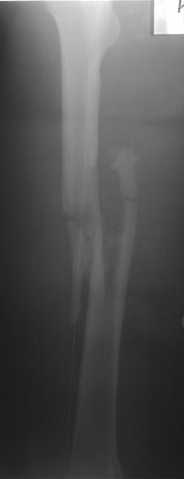

Судя по рентгенограмме и снимкам перелом "не очень высокоэнергетичный" - почему не рассматривать его как повреждение I по Gustilo с соответствующей тактикой? По фото значительных повреждений мягких тканей не наблюдается - или есть большое выходное отверстие?

Несмотря на высокоэнергетический характер ранения, пуля не попала непосредственно в кость, а прошла рядом. Таким образом, для бедренной кости это ранение нельзя назватьв полном смысле этого слова высокоэнергетическим. К сожалению, не видно выходное отверстие. В любом случае, при таком переломе интрамедуллярный остеосинтез вполне показан. Кроме того, если пациент попал к Вам в первые часы после ранения, рана не должна рассматриваться как инфицированная. В качестве примера возможности даже более травматичной операции при таком характере перелома привожу следующий случай.